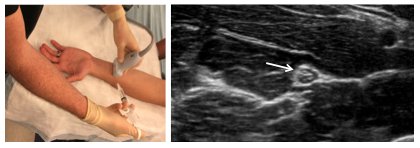

With a spinal needle attached to the anesthetic syringe, enter the skin 1 cm adjacent to the probe with the needle bevel up. Entry of the needle should generally be at a 45-degree angle.

To best visualize the needle tip, keep the probe in a transverse orientation and use an in-plane technique.

Advance the needle slowly, and aim toward the dorsal aspect of the hyperechoic (bright) nerve. Stay at least 1 cm from the nerve to avoid puncture.

Slowly inject 2 to 3 mL of anesthetic to confirm location. Anesthetic will have a hypoechoic (dark) appearance. If patient feels a sharp electric type pain with injection remove needle slightly and re-inject. Patient should feel pressure but not electric shooting pain.

Using V-shaped redirections of the needle, inject 2 to 5 mL of anesthetic per each nerve over the palmar and dorsal aspects of the nerve. The needle should not penetrate the nerve at any point.

- Full circumferential spread of anesthetic around the nerve is ideal but not required.

Visualize injection of the anesthetic at all times.